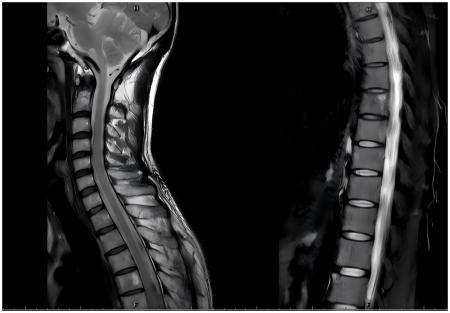

• MR:1.双侧肩袖间隙及腋隐窝肿胀增厚,关节周围滑膜增厚,周围软组织肿胀,考虑肩关节滑膜炎可能;2.双侧肱骨上段、部分胸腰椎椎体及附件、双侧骶骨及髂骨多发骨质异常改变,考虑肿瘤性病变可能。

6.png